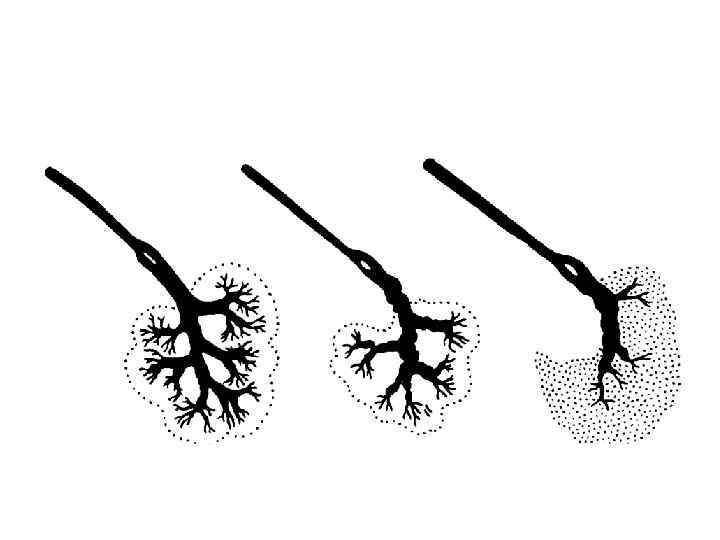

Слюноотделение • , саливация (лат. salivatio) • выделение слюнными железами слюны. • Слюноотделение крупных желез происходит рефлекторно • Мелкие слюнные железы секретируют постоянно, увлажняя слизистую оболочку.

Слюноотделение • в среднем за сутки выделяется 1— 2, 5 л слюны. • без стимуляции - около 0, 5 мл/мин. • Слюноотделение продолжается весь период еды и почти полностью прекращается вскоре после ее окончания.

Изменения слюноотделения • Гипосаливация, гипосиалия – снижение слюноотделения • Ксеростомия (греч. xēros сухой + stoma рот, отверстие) — сухость во рту. • Гиперсаливация, сиалорея, птиализм —избыточное слюноотделение